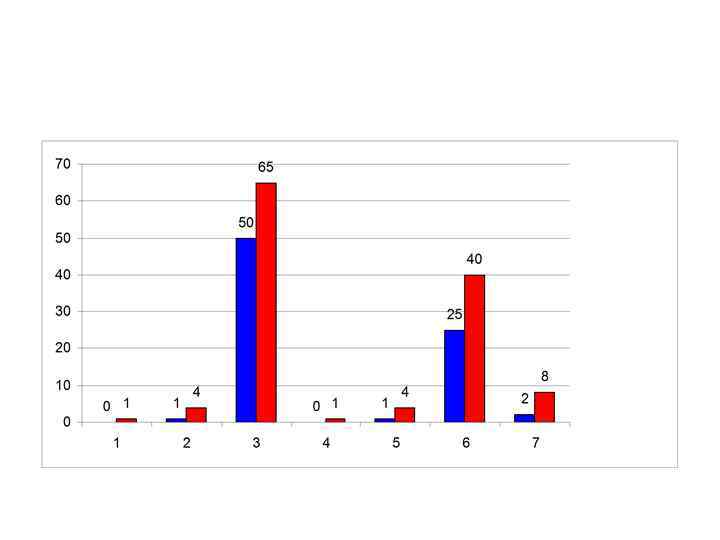

Кривая Прайс-Джонса • Для ее построения в окрашенном мазке крови при помощи окуляр-микрометра измеряют диаметр не менее 100 клеток. • По результатам этих измерений строят график, в котором по оси абсцисс откладывают величины диаметра эритроцитов в микронах, а по оси ординат - процент клеток с соответствующим диаметром.

Кривая Прайс-Джонса • Для ее построения в окрашенном мазке крови при помощи окуляр-микрометра измеряют диаметр не менее 100 клеток. • По результатам этих измерений строят график, в котором по оси абсцисс откладывают величины диаметра эритроцитов в микронах, а по оси ординат - процент клеток с соответствующим диаметром.

• Эритроцитометрическая кривая у здоровых людей имеет правильную треугольную форму с высокой вершиной и узким основанием. • Преобладают эритроциты с диаметром 6 -8 мкм, которые составляют 70 -75% всех эритроцитов. • На долю микроцитов (клетки диаметром меньше 6 мкм) и макроцитов (диаметр более 8 мкм) приходится приблизительно одинаковое количество (12 -15%), ширина кривой отражает степень анизоцитоза, а положение максимума - средний диаметр эритроцита.

• Эритроцитометрическая кривая у здоровых людей имеет правильную треугольную форму с высокой вершиной и узким основанием. • Преобладают эритроциты с диаметром 6 -8 мкм, которые составляют 70 -75% всех эритроцитов. • На долю микроцитов (клетки диаметром меньше 6 мкм) и макроцитов (диаметр более 8 мкм) приходится приблизительно одинаковое количество (12 -15%), ширина кривой отражает степень анизоцитоза, а положение максимума - средний диаметр эритроцита.

1 – микроцитоз, 2 - макроцитоз, 3 – мегалоцитоз при пернициозной анемии, 4 – анизоцитоз на фоне (жёлтом) нормальной кривой Прайс-Джонса.

1 – микроцитоз, 2 - макроцитоз, 3 – мегалоцитоз при пернициозной анемии, 4 – анизоцитоз на фоне (жёлтом) нормальной кривой Прайс-Джонса.

• При микроцитозе (характерном, например для железодефицитоной анемии) эритроцитометрическая кривая сдвигается влево, кривая становится асимметричной, ширина ее увеличивается. • При макроцитозе (например, сопровождающем В 12 и фолиеводефицитную анемию) кривая Прайс-Джонса сдвигается вправо, уплощается, основание ее расширяется. • Построение кривой Прайс-Джонса вручную - чрезвычайно трудоемкое занятие. • В то же время современные компьютерные системы анализа изображения (например, автоматизированное рабочее место врача-гематолога МЕКОС-Ц 1) быстро и с высокой точностью строят ее в автоматическом режиме. http: //unimedao. ru/hematology. htm

• При микроцитозе (характерном, например для железодефицитоной анемии) эритроцитометрическая кривая сдвигается влево, кривая становится асимметричной, ширина ее увеличивается. • При макроцитозе (например, сопровождающем В 12 и фолиеводефицитную анемию) кривая Прайс-Джонса сдвигается вправо, уплощается, основание ее расширяется. • Построение кривой Прайс-Джонса вручную - чрезвычайно трудоемкое занятие. • В то же время современные компьютерные системы анализа изображения (например, автоматизированное рабочее место врача-гематолога МЕКОС-Ц 1) быстро и с высокой точностью строят ее в автоматическом режиме. http: //unimedao. ru/hematology. htm